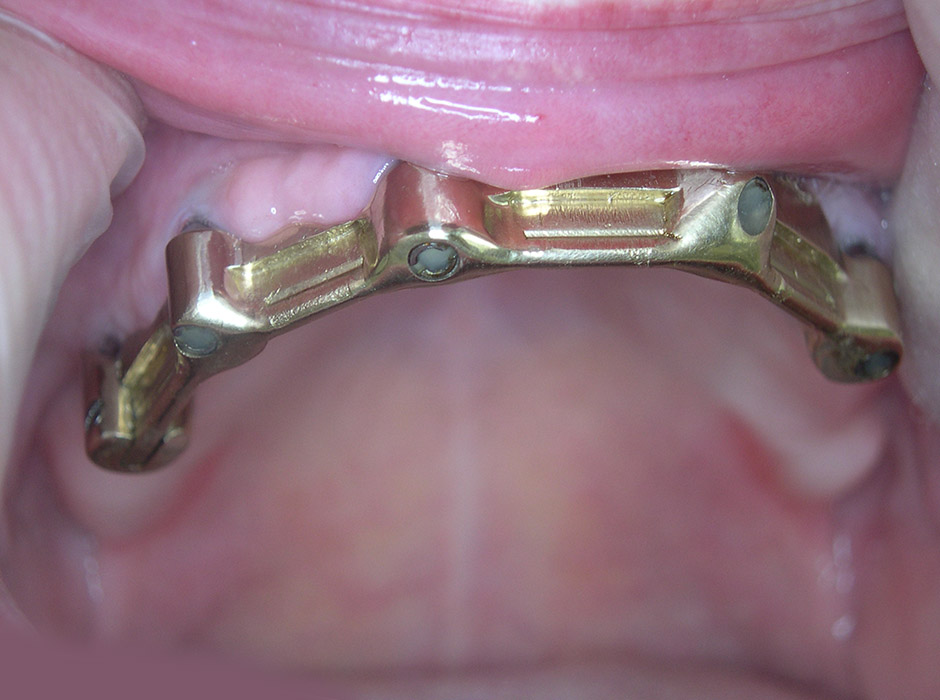

Aber auch Prothesenträger profitieren von Implantaten, da durch diese herausnehmbarer Zahnersatz sicherer zu verankern ist, was die Lebensqualität bedeutend steigert.